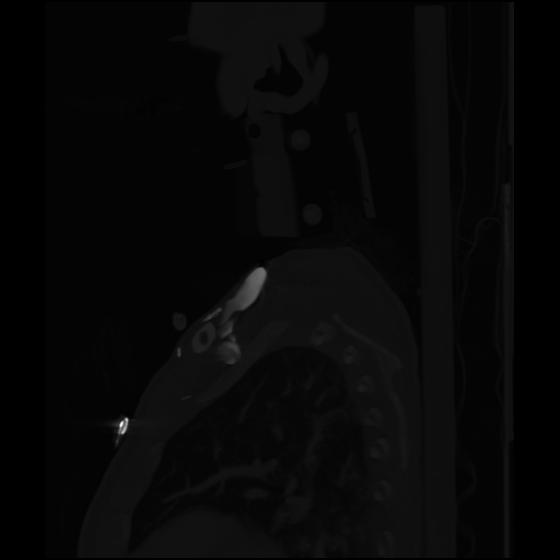

24 ANGIO,CE,Sag-MIP,5.000,ANGIO,Sag-MIP,